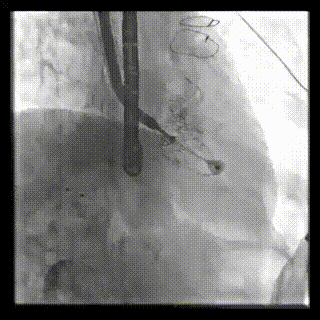

2021年12月24日,復(fù)旦大學(xué)附屬中山醫(yī)院葛均波院士團(tuán)隊(duì)成功應(yīng)用LuX-Valve Plus為一例極重度三尖瓣反流(TR)合并房顫、房缺的患者完成了經(jīng)血管三尖瓣置換術(shù),這是在前基礎(chǔ)上,本周完成的第三例經(jīng)血管三尖瓣置換手術(shù),葛均波院士、周達(dá)新教授等與心外科魏來教授、賴顥教授,心超室的潘翠珍教授、李偉教授及麻醉科的郭克芳教授共同完成了本周手術(shù),均獲得圓滿成功!患者術(shù)后超聲顯示無TR,臨床癥狀明顯改善。本周手術(shù)的成功也為LuX-Valve Plus救治性臨床研究添上了濃墨重彩的一筆。

本周三例接受LuX-Valve Plus經(jīng)血管三尖瓣置換術(shù)的患者中,第一例患者為冠狀動脈旁路移植術(shù)+Bentall+二尖瓣成形術(shù)后;第二例患者為永久起搏器植入術(shù)后,存在跨三尖瓣導(dǎo)線;第三例患者合并房顫、房缺及左心耳封堵術(shù)后。

三例患者入院后,葛均波院士團(tuán)隊(duì)周達(dá)新教授、潘文志教授、張?jiān)床┦?、陳莎莎博士及心超室的潘翠珍教授、李偉教授對患者的情況進(jìn)行詳細(xì)評估和討論,最終決定為三例患者選擇LuX-Valve Plus40mm、50mm和50mm型號的瓣膜進(jìn)行手術(shù)治療。手術(shù)后即刻拔除氣管插管,術(shù)后患者三尖瓣反流癥狀得到顯著改善,復(fù)查心超結(jié)果顯示人工三尖瓣瓣膜支架固定穩(wěn)定,瓣葉關(guān)閉形態(tài)未見異常,未見明顯反流。